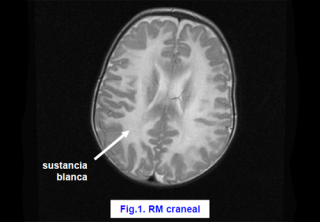

El niño/a va a desarrollar antes o después una grave enfermedad neurológica denominada degeneración espongiosa de la sustancia blanca o Enfermedad de Canavan.

La resonancia magnética craneal demuestra alteraciones de la sustancia blanca (leucodistrofia) muy características (degeneración en esponja de la sustancia blanca) (fig.1) y en la espectroscopia se observa un notable incremento del NAA (fig. 2).